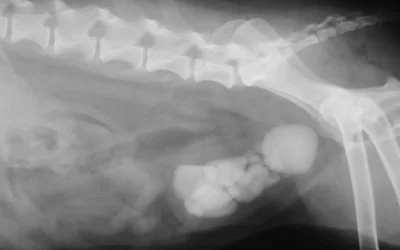

Calcoli nella vescica

I calcoli nella vescica del cane sono accumuli di minerali e altre sostanze che si formano nella vescica urinaria. Possono essere di varie...